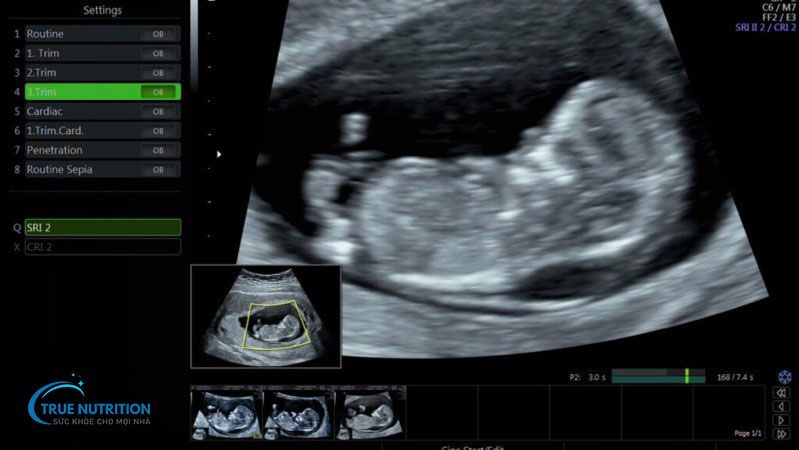

Độ mờ da gáy là khoảng chất lỏng tích tụ dưới da phía sau gáy thai nhi, được đo bằng phương pháp siêu âm trong những tuần đầu của thai kỳ. Đây là một trong những chỉ số quan trọng để đánh giá nguy cơ mắc các dị tật bẩm sinh, chẳng hạn như hội chứng Down, bất thường nhiễm sắc thể hoặc các vấn đề về tim mạch.

Thời điểm tốt nhất để thực hiện đo độ mờ da gáy là từ tuần thứ 11 đến tuần thứ 14 của thai kỳ. Trong giai đoạn này, độ mờ da gáy thể hiện rõ ràng và dễ đo lường. Trước tuần thứ 11, thai nhi còn quá nhỏ để có thể thu được kết quả chính xác. Sau tuần thứ 14, lượng chất lỏng dưới da bắt đầu giảm, làm giảm độ chính xác của phép đo.

Quá trình đo độ mờ da gáy thường được thực hiện bằng siêu âm qua bụng hoặc siêu âm đầu dò. Thao tác siêu âm đơn giản, không xâm lấn và an toàn tuyệt đối cho mẹ bầu cũng như thai nhi. Thời gian thực hiện chỉ kéo dài từ 15 đến 30 phút tùy thuộc vào vị trí của thai nhi.